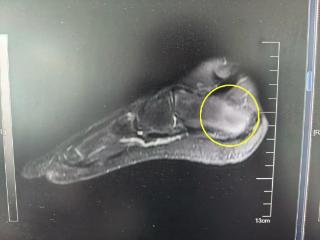

会分析、超能算,这个“医生助手”让诊疗过程智慧又高效